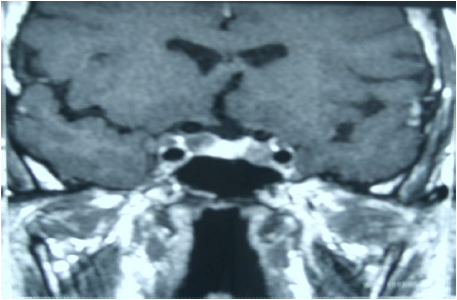

Observe a imagem de ressonância magnética, obtida em T1, plano coronal, e assinale a opção que indica o seguinte achado a ela correspondente: